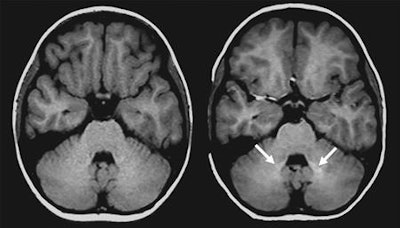

Young patients who received the gadolinium contrast agent showed greater signal intensity in the dentate nucleus on unenhanced T1-weighted MR images, compared with children who never received the contrast agent. The findings are of particular concern because pediatric brains are still developing, and these children may be exposed to additional gadolinium in future scans, depending on their illness.

All subjects were imaged on a 1.5-tesla whole-body MRI scanner (Avanto, Siemens Healthineers), which included an unenhanced axial T1-weighted spin-echo sequence. Measurements of signal intensity were taken within the globus pallidus, thalamus, dentate nucleus, and pons, with a mean diameter of 5 mm (range: 3-9 mm).

Flood and colleagues discovered higher signal intensity in the dentate nucleus among patients who previously received multiple GBCA-enhanced exams (mean ratio, 1.046 ± 0.006), compared with subjects who had not received contrast (mean ratio, 1.007 ± 0.0058). This result is similar to what has been confirmed in adult patients.

However, there was no such signal intensity increase in the globus pallidus in the GBCA-exposed group (mean ratio, 1.014 ± 0.0091), compared with the GBCA-free subjects (mean ratio, 1.131 ± 0.0070).